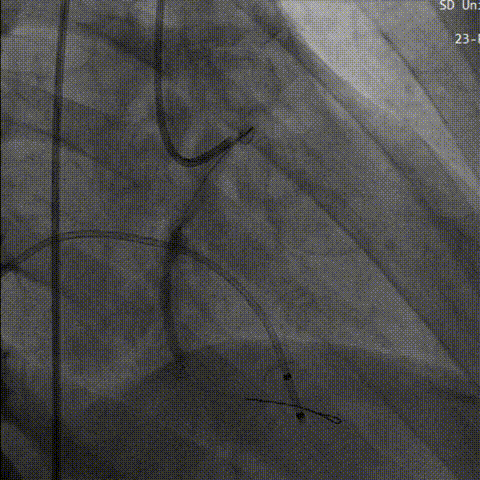

直头导丝跨瓣

行成功跨瓣后,术者团队用23mm球囊预扩,结合瓣环及球囊预扩情况,植入预装AV26型号瓣膜。

球 囊 预 扩